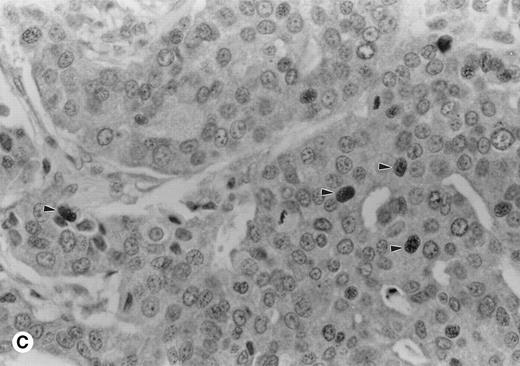

A variety of tissues were sampled for expression of cyclin A1 using immunohistochemistry on formalin- and B5-fixed paraffin-embedded sections. One case of acute promyelocytic leukemia showed strong 3+ nuclear staining in almost all leukemic cells (Fig 1A). In contrast, normal marrows had few positive cells with weak nuclear staining (Fig 1B). Cyclin A1 was also localized in a few solid tumors (Table 1). One case of adenocarcinoma of the colon showed speckled nuclear staining (Fig 1C). In contrast, the normal colonic mucosa showed only rare positive cells in the epithelium at the base of the crypts (data not shown). We were particularly impressed by strong expression in the promyelocytic leukemia shown in Fig 1A, which prompted us to investigate further the expression of cyclin A1 in leukemia samples.

Immunohistochemistry showing cyclin A1 expression in tissue sections. (A) Bone marrow biopsy from a case of acute promyelocytic leukemia (AML M3). Promyelocytes show strong nuclear staining for cyclin A1. (B) Normal bone marrow biopsy with negative or focal weak staining of myeloid precursors. (C) Adenocarcinoma of the colon with malignant cells showing nuclear staining for cyclin A1 (arrowheads). Hematoxylin counterstain original magnification × 400.